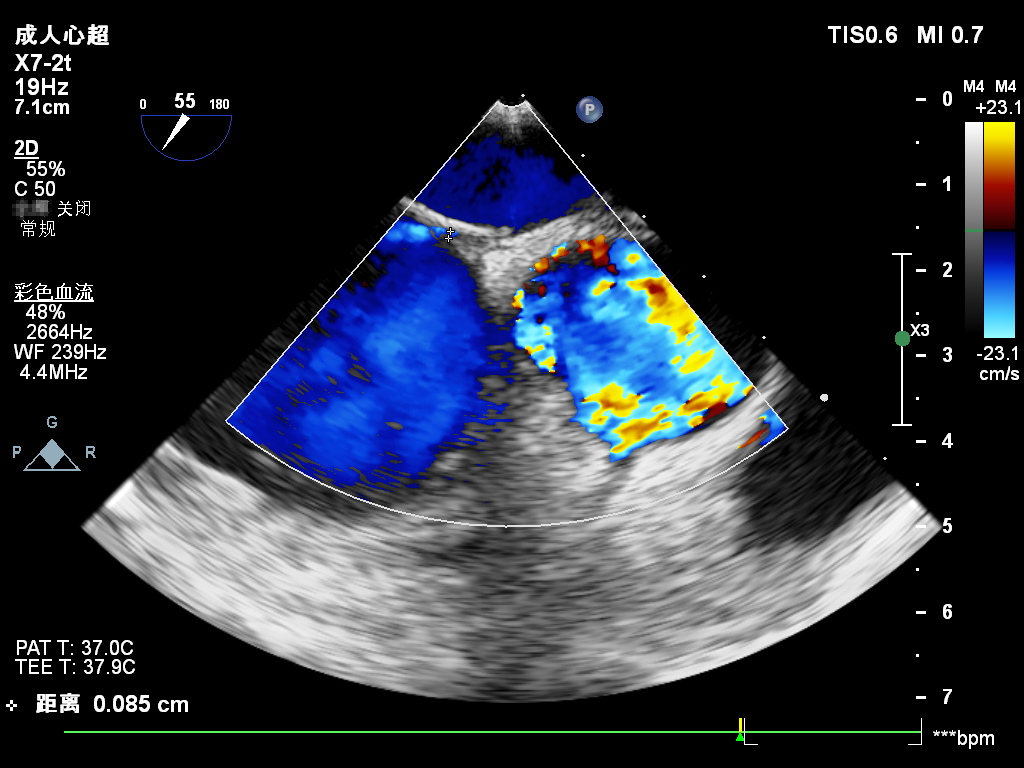

本例患者靜息狀態下PFO隧道長度7.96mm,開口0.85mm,故選用D-shufo 1824-3封堵器,配套9F封堵器介入輸送系統,完成手術封堵。

超聲觀察對周圍組織無影響

封堵器釋放后成型良好,無殘余分流